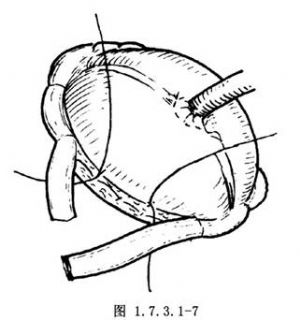

6.如估计用上述方法不能满意地解除梗阻,准备术后切开盲肠减压时,可将腹壁切口的壁层腹膜与皮肤的真皮层行间断缝合(图1.7.3.1-6)。最后,将盲肠的浆肌层与壁层腹膜缝合,以此缝线结扎凡士林纱布条(图1.7.3.1-7)。最后用凡士林纱布覆盖。